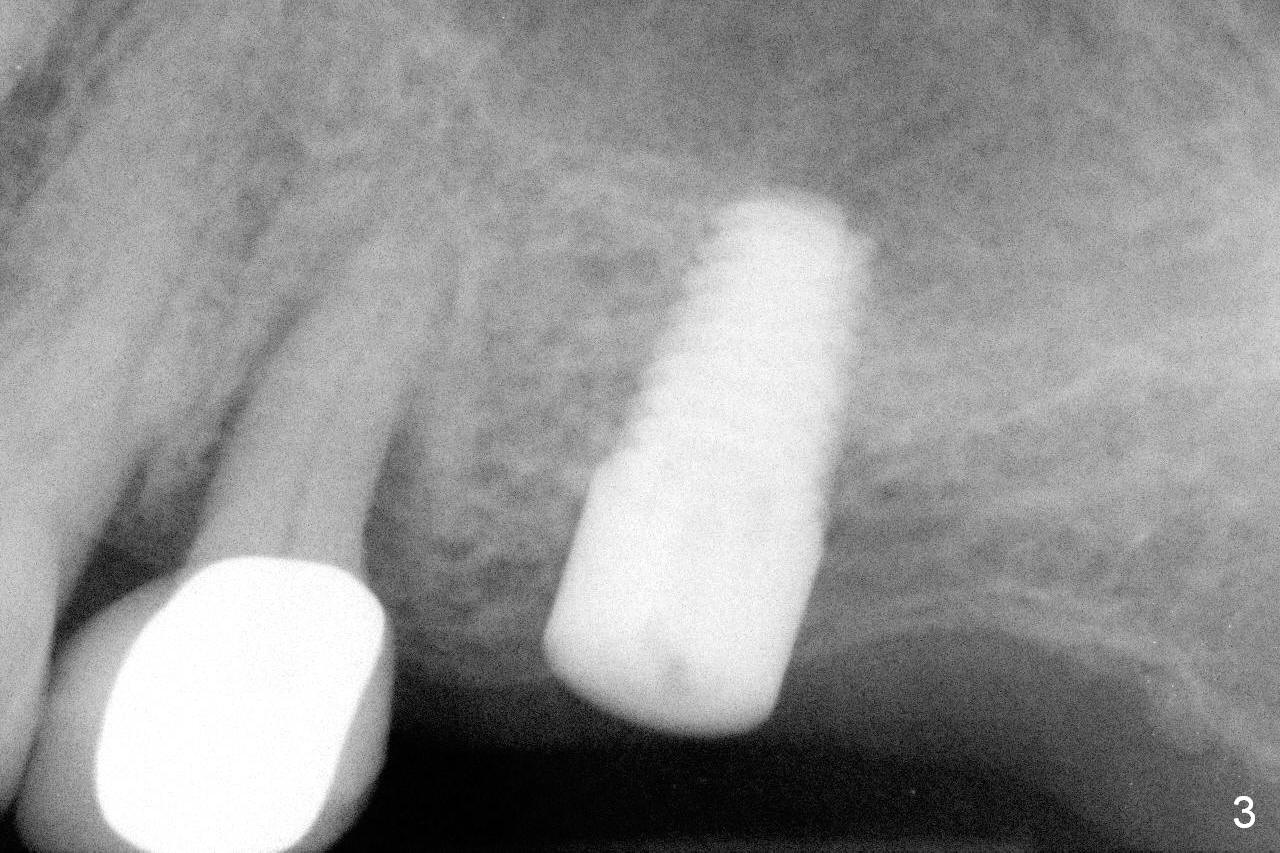

A 73-year-old woman is a possible bruxer with partial edentulism; the tooth #13 had increased periodontal ligament (pdl) space 4 years ago (Fig.1 *).  A 5x14 mm tissue-level implant is placed at the site of #14 (Fig.2).  The implant appears to be osteointegrated in 6 months (Fig.3).  There is crestal bone loss 8 months post cementation (Fig.4 *).  The persistent increased pdl at #13 is most likely associated with occlusal tramua from the tooth #19 (Fig.5 (13 months post cementation of #14)).  Three years post #14 cementation, the tooth #13 has mobililty II (Fig.6); bone density increases around the apical half of the implant (arrowheads).  Normally bone density is the highest coronally where functionality dictates.  This indicates the bone loss is getting worse at #14 as well.